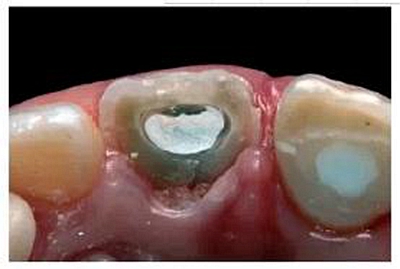

去除殘留的復(fù)合樹脂后,輕輕去除10mm長的牙膠,操作時盡量避免損傷薄弱的根管壁。根據(jù)所需長度,選擇6號成品FRCP放入根管內(nèi)。由于根管口較大,樁和根管壁間無法獲得足夠的固位力(圖12)。但填入樹脂粘接劑后,樁和根管壁之間的間隙則不會對FRCP的性能產(chǎn)生較大影響。粘接前需用乙醇清洗纖維樁表面。

根據(jù)前文中的研究結(jié)果,我們決定結(jié)合使用LB和LCZ。根管內(nèi)先進(jìn)行酸蝕處理。大量無菌蒸餾水沖洗根管,去除磷酸酸蝕劑后,干燥根管。根據(jù)產(chǎn)品說明再度潤濕根管,這一步對重建塌陷的膠原纖維網(wǎng)是非常有必要的,這能確保丙酮類粘接系統(tǒng)的最佳滲透力。根據(jù)產(chǎn)品說明,和應(yīng)用于牙本質(zhì)一樣,在樁和根管內(nèi)使用PreBond以及BondA和BondB的混合劑。當(dāng)將LCZ充入根管內(nèi)時,樁和粘接材料充分接觸,使樁表面達(dá)到最佳表面潤濕。將FRCP放入根管,去除根管多余樹脂,光照固化(2000 mW cm-2;MiniLED III; Satelec Acteon Equipment, Merignac,F(xiàn)rance)。